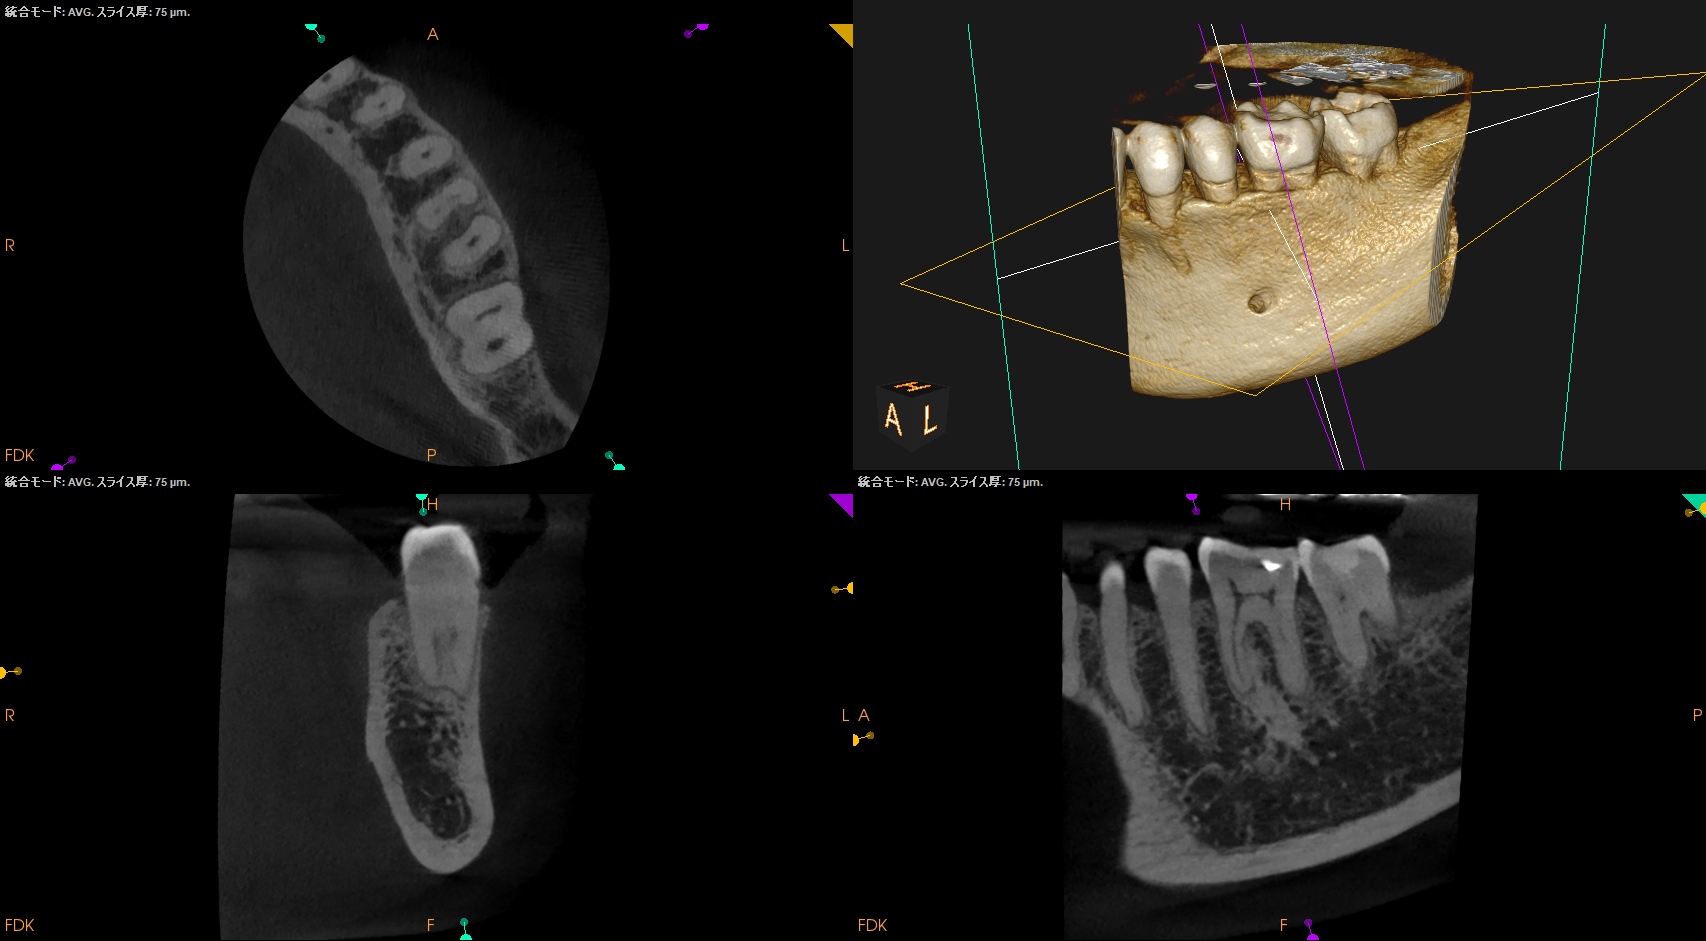

チャンバーオープンした。

やはり血まみれだ。

以下のように根管形成した。